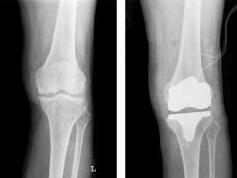

2、种类:人工关节分为全关节和半关节置换两种类型,全关节置换是指替换整个关节,而半关节置换仅替换关节的一部分。

4、植入人工关节:将选择合适的人工关节植入骨骼中,确保其稳定性和合适的位置。